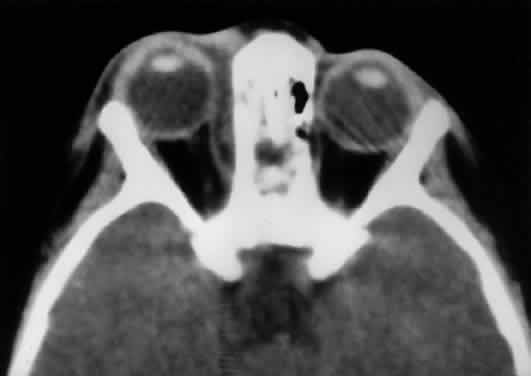

closure.  Fig. 18. Carotid-cavernous fistula. A. Clinical photograph demonstrating tortuosity of the arteriolized episcleral

veins, extending up to the limbus (the vascular congestion of conjunctivitis

usually ends 1 mm short of the limbus). B. Axial CT shows the difference in caliber between the uninvolved superior

ophthalmic vein and the involved vein (arrows). C. Coronal image likewise shows the difference in venous size (arrows). Also note the enlargement of the extraocular muscle on the involved

side, indicative of orbital congestion. The superior ophthalmic vein is

always found beneath the superior rectus muscle, to which it is tethered

by a hammock-like fascial slip. On the involved side, orbital congestion

and enlargement of the vein cause distortion of this anatomic

relation. D. Parasagittal arteriography image of a different patient shows abnormal

arterial filling of the CS, extending anteriorly into the orbit through

an engorged superior ophthalmic vein (SOV). Fig. 18. Carotid-cavernous fistula. A. Clinical photograph demonstrating tortuosity of the arteriolized episcleral

veins, extending up to the limbus (the vascular congestion of conjunctivitis

usually ends 1 mm short of the limbus). B. Axial CT shows the difference in caliber between the uninvolved superior

ophthalmic vein and the involved vein (arrows). C. Coronal image likewise shows the difference in venous size (arrows). Also note the enlargement of the extraocular muscle on the involved

side, indicative of orbital congestion. The superior ophthalmic vein is

always found beneath the superior rectus muscle, to which it is tethered

by a hammock-like fascial slip. On the involved side, orbital congestion

and enlargement of the vein cause distortion of this anatomic

relation. D. Parasagittal arteriography image of a different patient shows abnormal

arterial filling of the CS, extending anteriorly into the orbit through

an engorged superior ophthalmic vein (SOV).